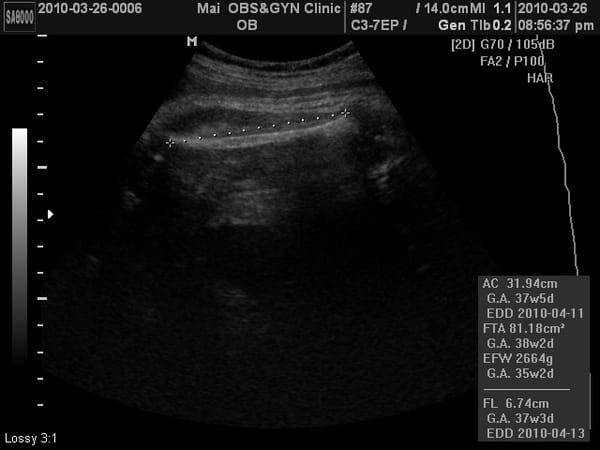

小老虎上次產檢2500公克,這次2600多公克,這兩周吃的東西都長在媽媽身上。

小老虎的大腿骨。